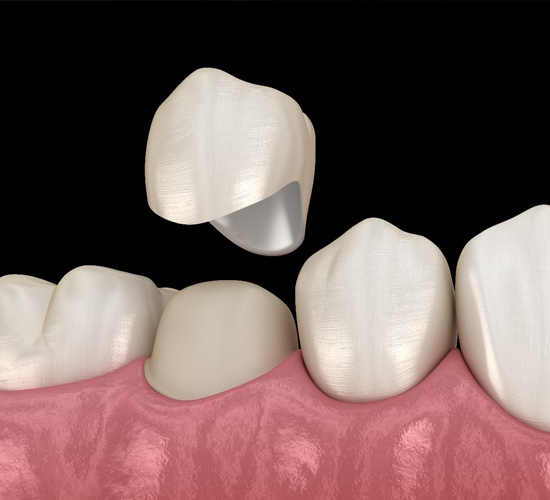

If you receive a dental crown or fixed bridge via a traditional procedure, you may have to wait weeks before your restoration is in place.

Zirconia Dental crowns are caps that cover a tooth or a dental implant. Dentists often recommend crowns as a way to support broken, weak, or misshapen teeth.